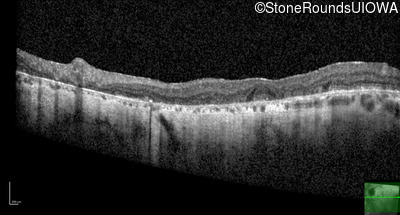

Foveal Hypoplasia (IIIG)